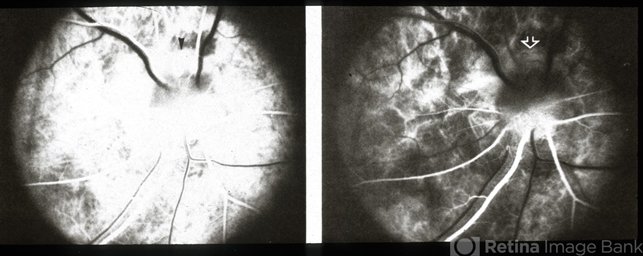

- inferior conus of optic nerve

- Fluorescein showing delayed filling in lower half, the area of conus.